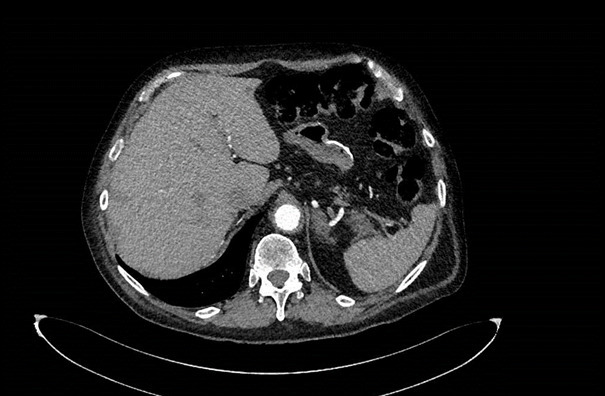

On voit sur ce scanner un aspect d’épaississement de la paroi aortique, signant la présence d’une aortite. L’anamnèse est évocatrice d’artérite à cellules géantes (ACG) avec la présence de signes céphaliques. Cette pathologie s’associe parfois à une aortite qui peut évoluer vers des complications à long terme, par exemple anévrisme et dissection, qu’il convient de dépister (scanner ou TEP scanner) et de suivre. La posologie de prednisone était probablement insuffisante dès le départ (0,5 mg/kg si PPR isolée, 0,7 mg/kg si ACG avec signes céphaliques, 1 mg/kg si atteinte ischémique).